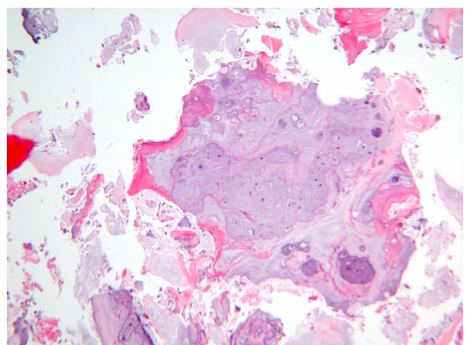

What is this?

Chondrosarcoma

More cellular/pleomorphic nuceli than enchondromas

Myoxid changed matrix